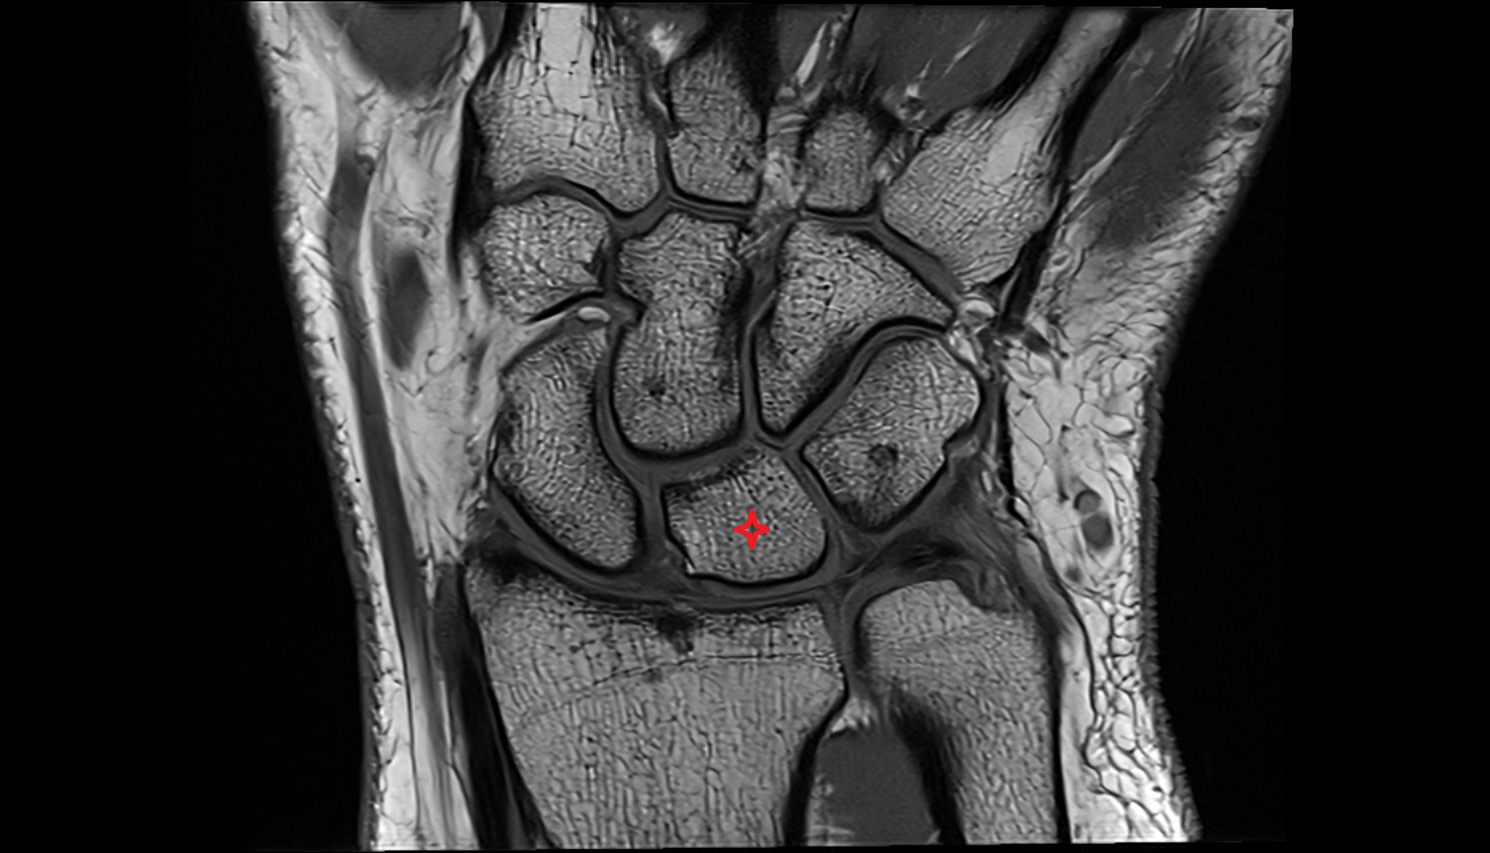

- Fetal wrist